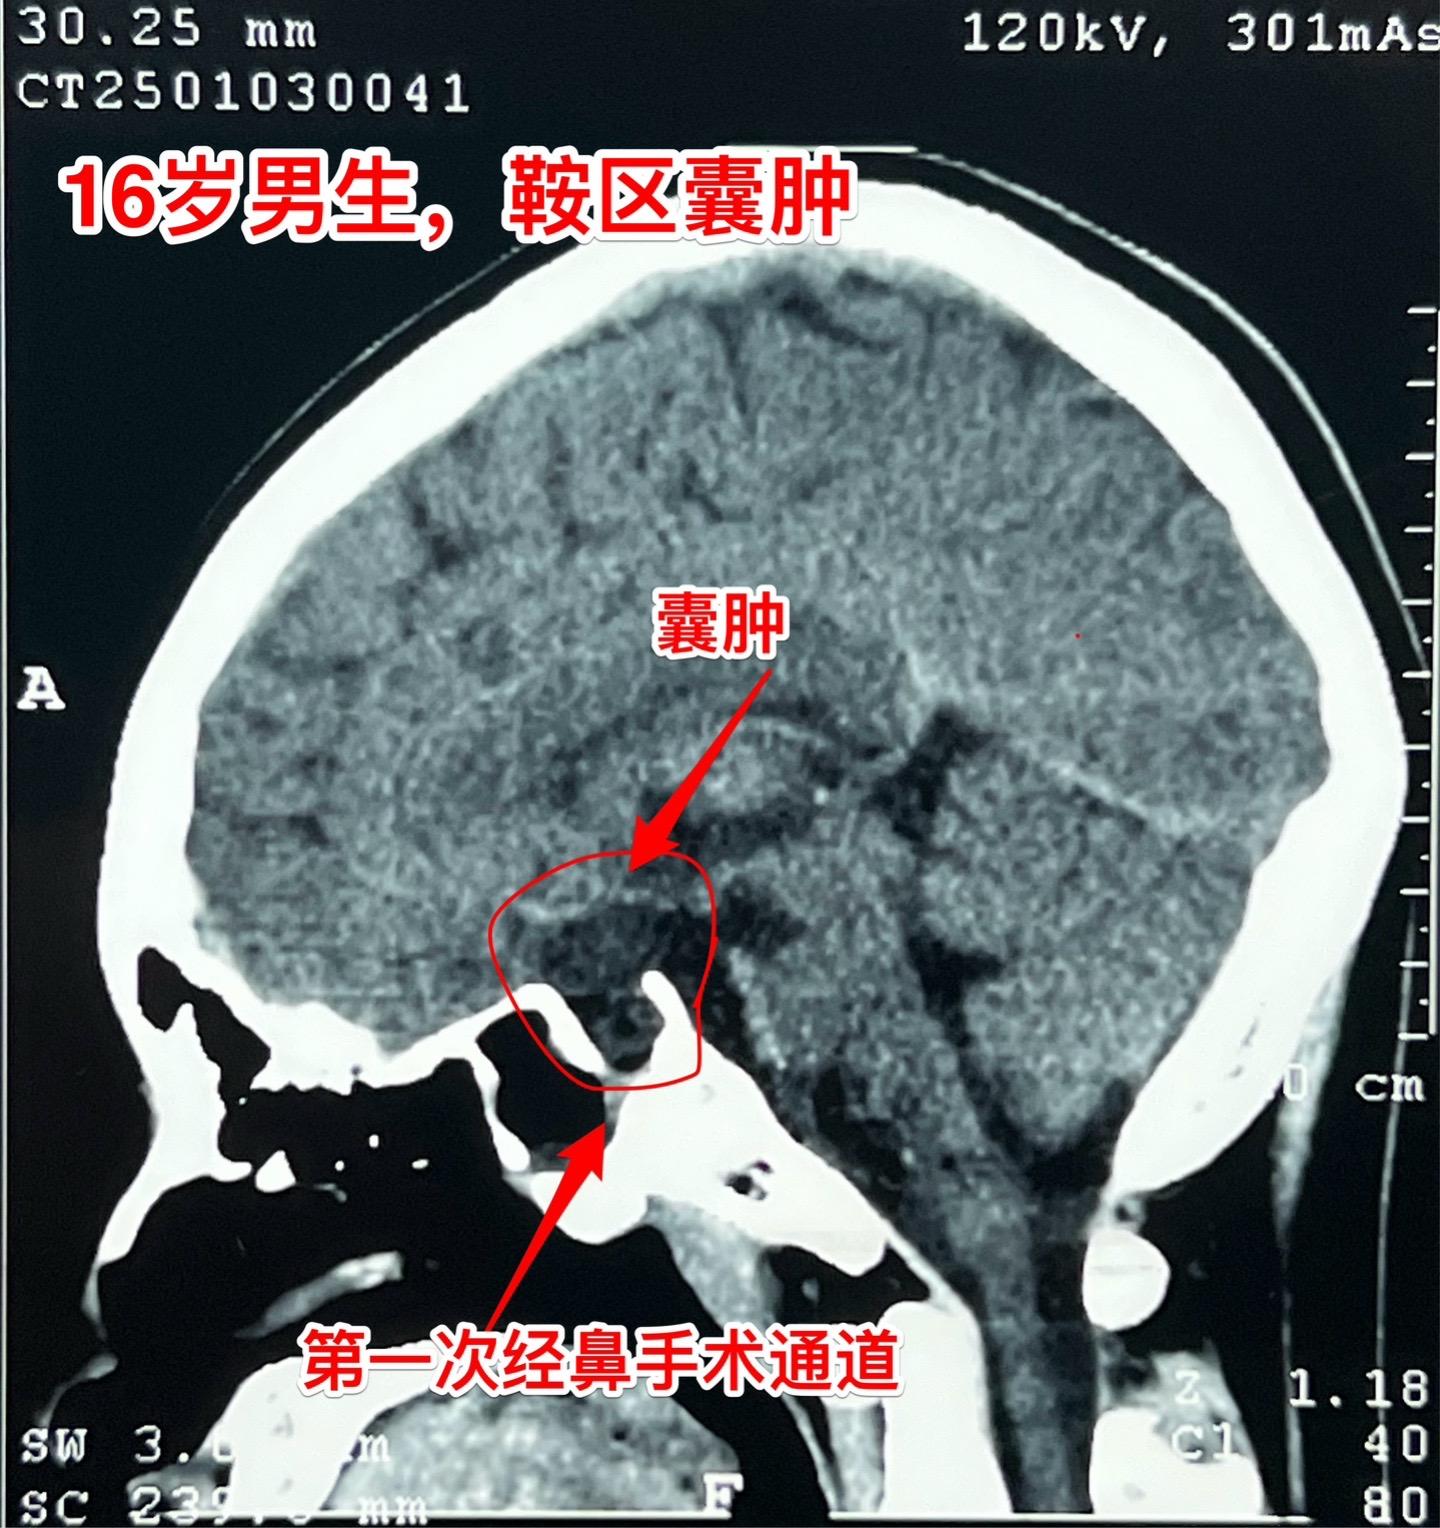

鞍区囊肿不能说是小问题(确诊拉克氏囊肿)16岁的男孩子2年前就因多饮多尿症状到医院检查发现鞍区囊肿,怀疑是拉克氏囊肿。这个病不是真性肿瘤,但是也不是小问题,也会导致尿崩症、生长发育迟缓、视力下降等问题。 他们一家选择了一个著名的医院去作手术,采用经鼻手术方式。遗憾的是手术中取得的标本最终未得出确切的病理诊断。手术后小孩子还出现了脑脊液鼻漏、颅内感染,受老罪了。 随后两年多时间内多次复查磁共振显示囊肿复发了,而且出现视力下降。然而小孩子对于第一次手术的痛苦印象太深了,故而拒绝作第